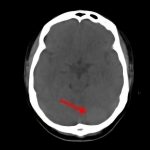

断層撮影

手術前1

手術前2